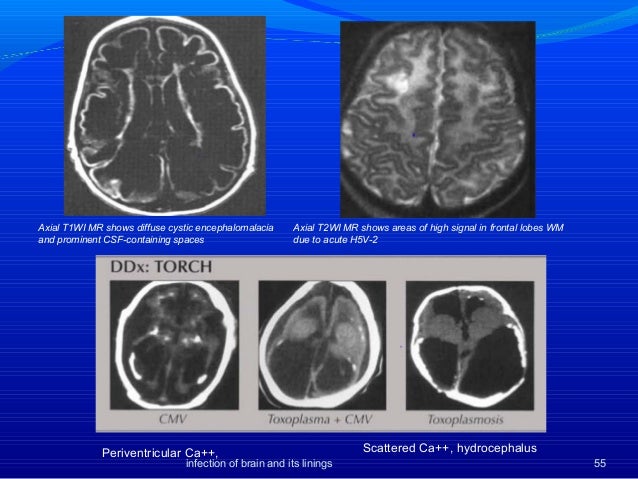

In many cases, the surgical removal of the softened brain matter does not give rise to any serious problems. Nov 2 20Encephalomalacia is a severe brain condition which can lead to serious brain damage and impair its functioning. Encephalomalacia - Definition, Symptoms, Prognosis, Treatment Sunada Y, Nishimura Y, Motoyoshi Y. Encephalomalacia Symptoms, Definition, Prognosis, Treatment Encephalomalacia Periventricular leukomalacia (PVL) is a histopathological term that does not imply a particular etiology and typically affects the immature brain over a limited gestational age range of 26weeks.

He had developed normally until he fell into the shock state induced by mismatch blood transfusion at the age of months. A case of multicystic encephalomalacia found in adult life was described.